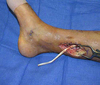

A 40-year-old man is brought to the emergency department because of a grade IIIB open fracture of the right distal aspect of the tibia and fibula sustained during a motorcycle collision. The plastic surgeon is consulted after initial debridement and external fixation of the fracture. Examination shows a 10-cm open wound of the right medial ankle with complete transection of the tibial nerve. The tibia fracture is comminuted but without marked bone loss. The foot is well perfused, but single-vessel run-off through the anterior tibial artery is noted. Which of the following is the most appropriate management of this patient’s condition?

The correct response is Option C.

The answer is debridement with repair of the tibial nerve and coverage with an anterolateral thigh (ALT) free flap. This patient is presenting with a grade IIIB open fracture of the distal tibia and fibula with an open medial wound. Traditionally, lower extremity injuries with an insensate plantar foot were considered unsalvageable. However, more recent data have demonstrated that an insensate foot by itself should not be considered a contraindication to limb salvage if repair is otherwise possible. Studies have shown equivalent long-term outcomes with limb salvage and primary amputation and that half of the patients with tibial nerve injuries will regain plantar sensation within two years post-injury. This vignette describes a situation in which one could reasonably expect a successful outcome.

The size and location of the wound are most amenable to coverage with a microvascular free flap. In this instance, a fasciocutaneous flap will provide adequate soft-tissue coverage with minimal donor morbidity and potentially better long-term outcome if secondary bone grafting or hardware revision is required.

The reverse sural fasciocutaneous is a versatile flap that can be used for reconstruction of many different wounds of the distal lower extremity. The flap is a neurocutaneous flap supplied by the vascular axis of the sural nerve as well as distal peroneal artery perforators. In this case, the peroneal artery was damaged from the trauma and the pedicle of the flap is in the zone of injury, making it an inappropriate choice for reconstruction when better options are available.

The use of biologic materials such as bilaminar acellular dermal regeneration templates have been used successfully to cover wounds with exposed vital structures such as bone, tendon, and nerve. However, its use is best suited for smaller wounds or in patients in whom microvascular reconstruction is contraindicated or not desired. This patient required soft-tissue coverage over a major nerve repair and a comminuted fracture with internal hardware. A microvascular free flap would be the method of choice in this patient when feasible.

As stated previously, up to fifty percent of patients with tibial nerve injuries will recover plantar sensation after nerve repair. Nerve repair should be attempted to improve the overall outcome.